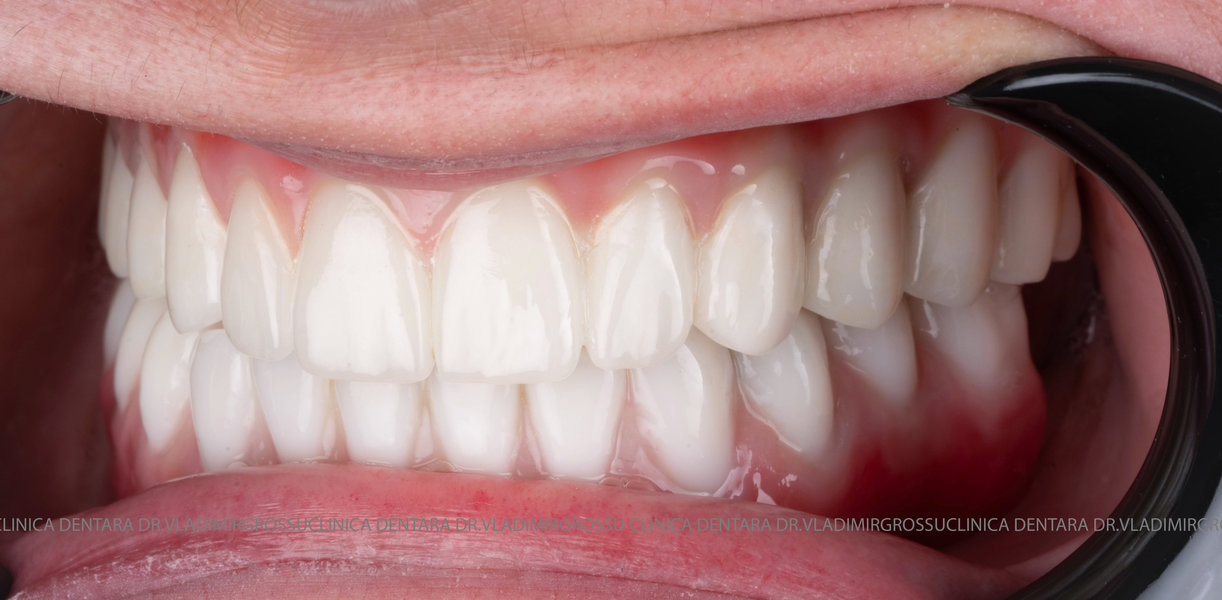

Această metodă este recomandată pacienților edentați total sau celor cu lipsuri dentare multiple. Procedura se realizează într-o singură etapă, iar pacientul primește proteza provizorie în ziua următoare intervenției. De regulă, proteza provizorie este realizată din masă plastică frezată. Suturile se îndepărtează după 5-7 zile.

La aproximativ 6 luni de la prima etapă, pacientul revine pentru protezarea definitivă. În această fază, medicul lucrează la nivelul multiunit-urilor și nu direct pe implanturi, ceea ce reduce riscurile pentru implant în etapa protetică.

Pentru proteza definitivă:

- 4 abutment-uri permanente pe multiunit-uri;

- Proteză definitivă din metaloceramică sau zirconiu pe o structură metalică, cu 12 unități (soluția recomandată).